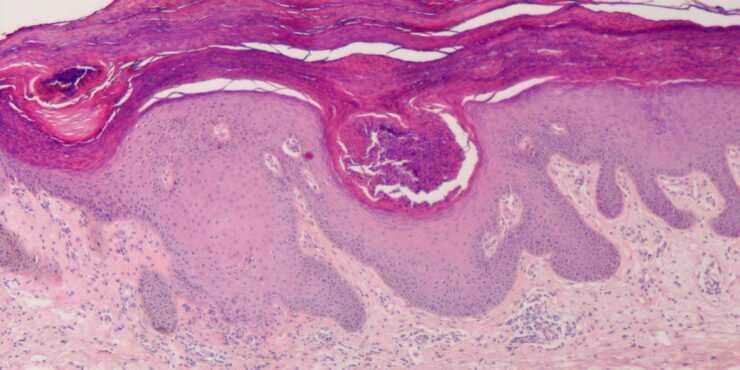

Graft versus Host Disease =داء رفض الطعم للمضيف Graft Versus Host Disease GVHD occurs in situations in which donor immunocompetent T cells transferred into allogenic hosts are incapable of rejecting them. The sources of the T cells include primarily peripheral blood stem cell and bone marrow transplants and, infrequently, unirradiated blood products , solid organ […]